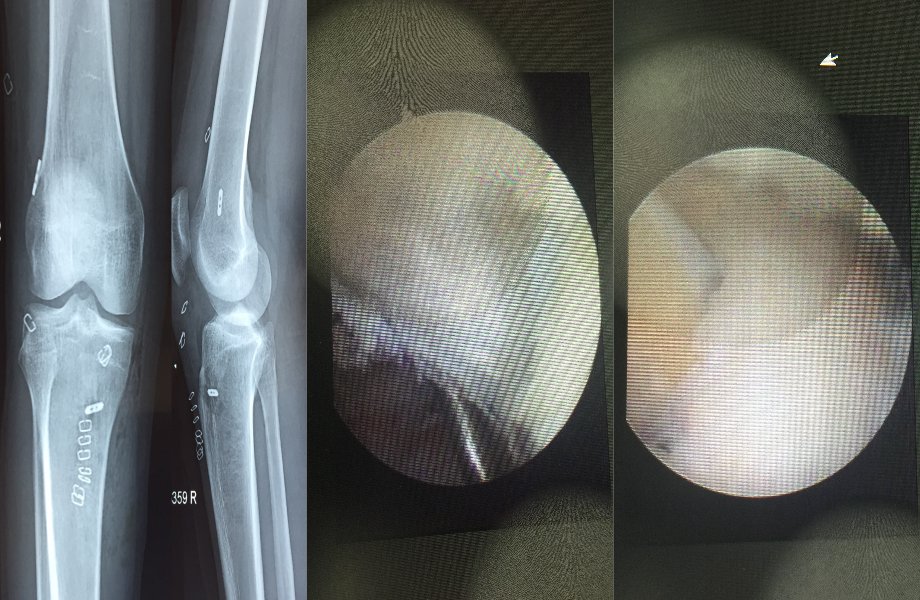

Arthroscopic Ligament Reconstruction

Arthroscopic Multiligament Reconstruction